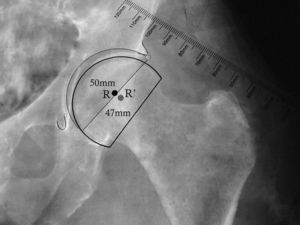

En las artroplastias bipolares, el plantillado del componente acetabular se reemplaza por el de la copa bipolar. El diámetro externo de esta copa debe ser ligeramente mayor al diámetro óseo de la cabeza femoral (fig. 3). Una vez marcado el centro de rotación de la copa bipolar, se procede al plantillado femoral. Frecuentemente, al utilizar una HA, el centro de rotación es ligeramente más caudal y lateral que al realizar un reemplazo total.

Plantillado de la copa bipolar. La imagen muestra la posición más caudal y lateral del centro de rotación de la copa bipolar en comparación con el centro de rotación del componente acetabular. También se muestra el menor diámetro de la copa bipolar (47mm) al compararlo con el componente acetabular (50mm). R: centro de rotación de componente acetabular; R’: centro de rotación de copa bipolar.